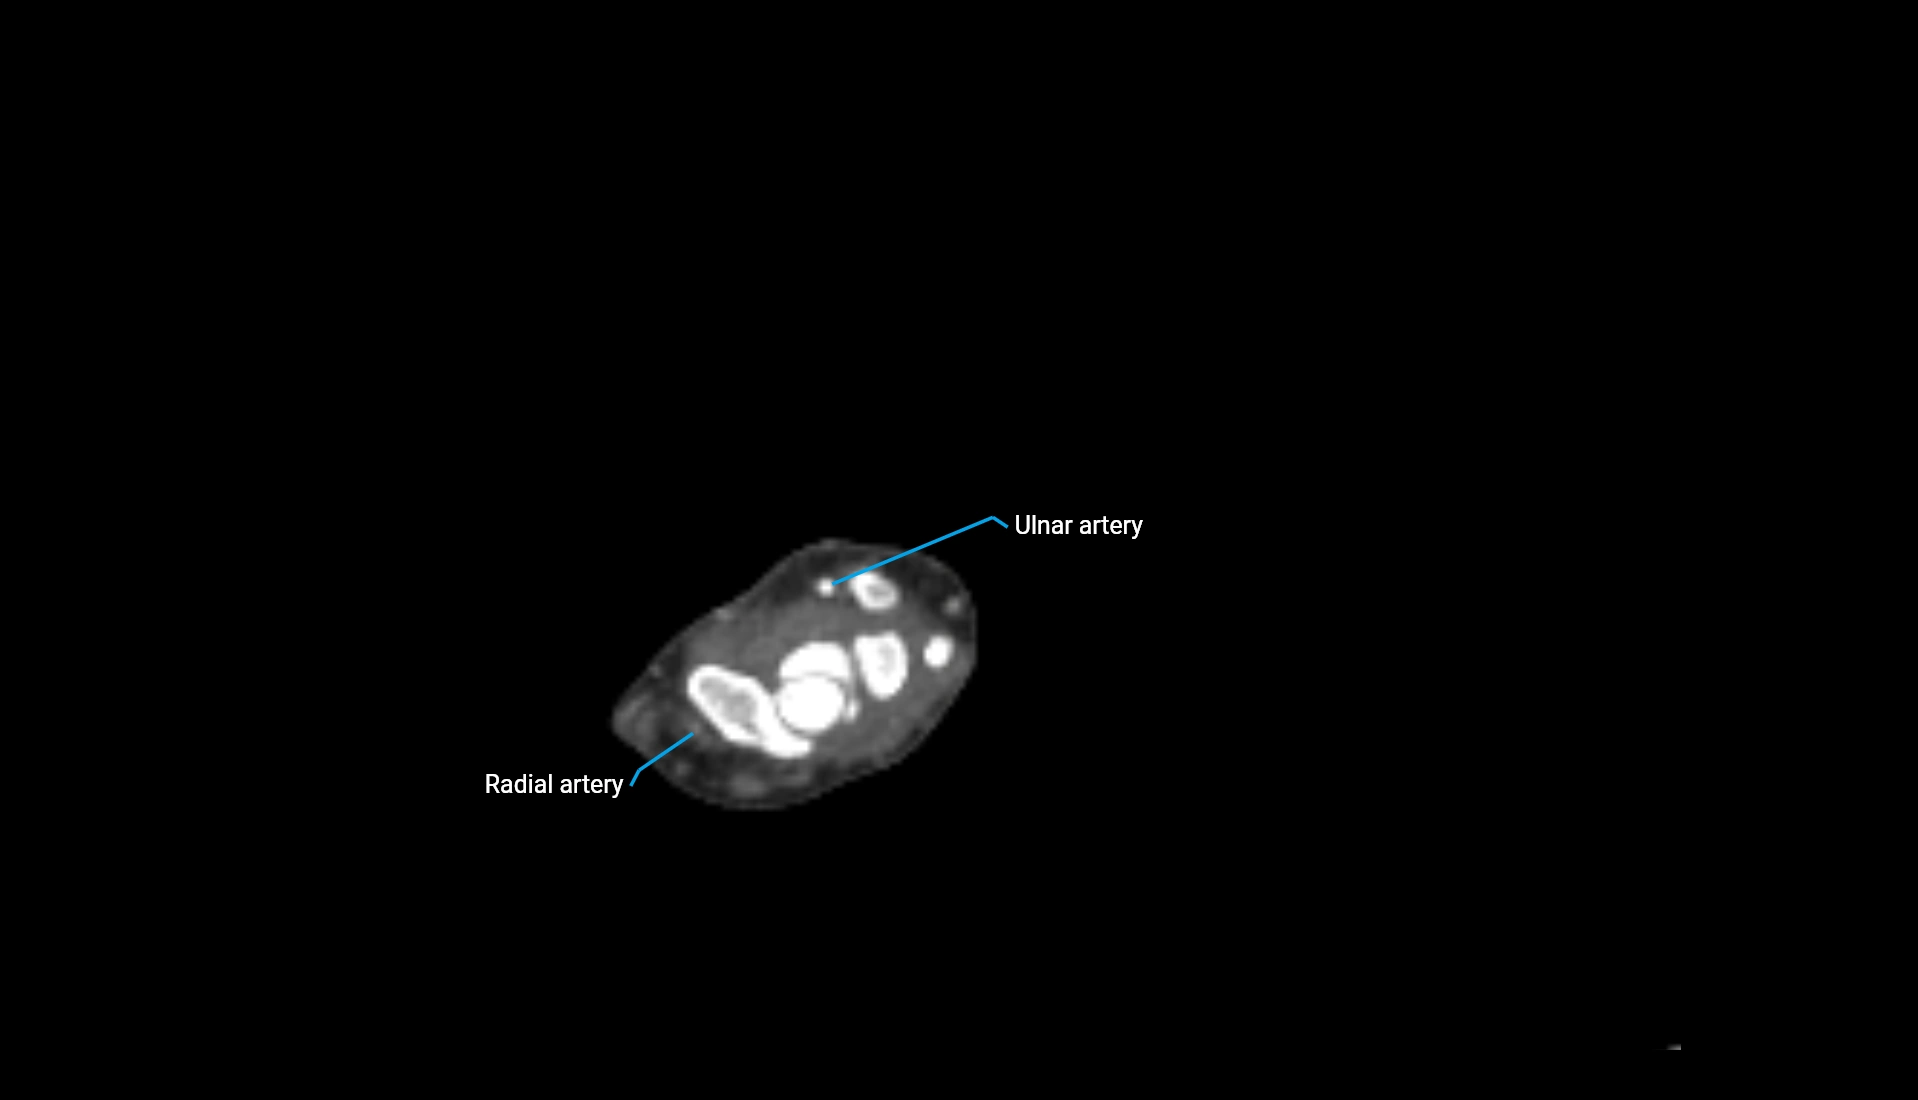

CT Appearance

Non-Contrast CT:

• Cortex: High-density, sharply defined

• Subchondral bone: Dense cancellous matrix

• Articular surface: Smooth concave contour articulating with the capitellum

• Excellent for evaluating bone integrity, alignment, and subtle fractures